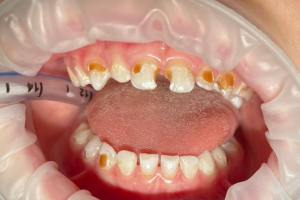

Семейная областная стоматология "Кидди Дентал" - это команда компетентных врачей, каждый из которых знает и любит свое дело. Опыт наших врачей, использование современного оборудования и надежных материалов позволят проводить лечение любой сложности.